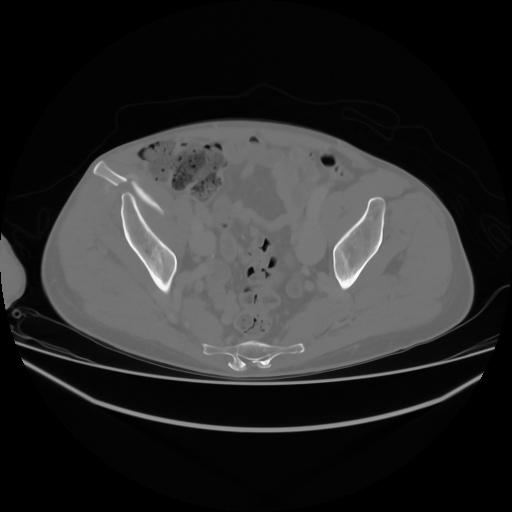

4 CUERPO,CE,Axial,3.0,CUERPO,,